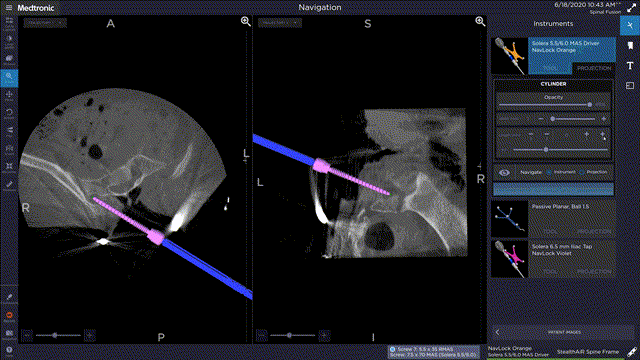

美敦力称,作为脊柱手术微创化理念的坚决拥护者和倡导者,团队在这一领域中会不断加码和打造全新的脊柱微创手术理念。其在Stealth Station S8导航及Mazor™ X脊柱手术机器人两大平台中,整合了基于脊柱手术流程的专用内固定系统方案,在全力打造未来微创手术安全、精准、高效的同时,更加锁定在脊柱微创手术流程的自动化和智能化。

在畸形手术中,结合Stealth导航技术的可视化置钉大幅提高了手术的效率和精准度。国际畸形研究协会(SRS)将基于Stealth导航可视化技术的手术流程向所有开展畸形手术的中心推荐,认为该技术可以有效的帮助脊柱外科应对突发和高难度手术带来的挑战。

据介绍,随着导航和内固定技术难关攻克,即使是脊柱肿瘤手术中的截骨和可撑开人工椎体重建流程,也可以在导航全程可视化下完成手术操作,大大提高脊柱肿瘤手术中的安全性的精准性。